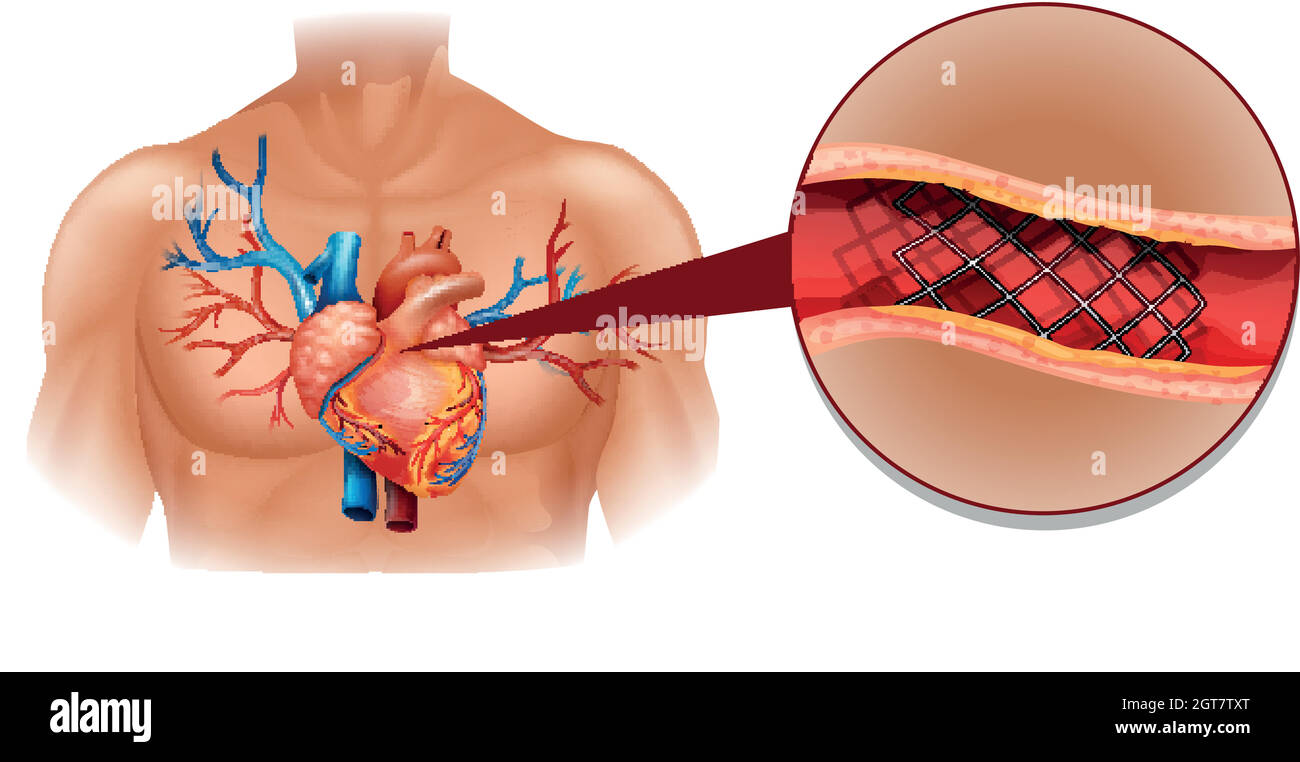

Heart disease diagram in human Stock Vectorhttps://www.alamy.com/image-license-details/?v=1https://www.alamy.com/heart-disease-diagram-in-human-image445184176.html

Heart disease diagram in human Stock Vectorhttps://www.alamy.com/image-license-details/?v=1https://www.alamy.com/heart-disease-diagram-in-human-image445184176.htmlRF2GT7TXT–Heart disease diagram in human